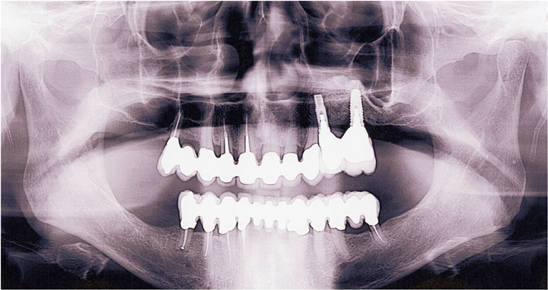

Figure 21 Panoramic radiograph showing the advanced bone loss for the fractured mandibular left second bicuspid. Pneumatization of the maxillary right sinus is noted, as is supra-eruption of posterior teeth.

Figure 21

This patient previously presented with esthetic concerns but was reluctant to proceed with reconstructive dental treatment (Figure 19 and Figure 20). She had been monitored for several years and advised of the benefits of an interdisciplinary treatment plan including periodontal, dental implant, and prosthodontic therapy. The diagnosis included occlusal trauma, loss of vertical dimension, lack of posterior tooth support, and supra-eruption. There was also gingival asymmetry, lack of attached gingiva, lateral ridge defect for the mandibular left molar region, pneumatization of the maxillary right sinus, and alloy tattoo of the gingiva for the maxillary right bicuspids. Eventually the mandibular left second bicuspid, which was an abutment for a fixed partial denture, fractured, resulting in an abscess and significant bone loss localized to this abutment tooth (Figure 21). At this point, given the need for extraction and now more limited posterior chewing capability, the patient requested a comprehensive consultation and treatment plan for the reconstructive therapy she had previously elected to postpone.

The first step was the emergent management of the fractured mandibular left bicuspid. This tooth was extracted and a ridge preservation procedure was performed for this site. There was advanced bone loss with the intrabony defect adjacent to the fractured root extending 6 mm. The site was grafted with a growth factor-enhanced bone matrix combining freeze-dried bone allograft (RegenerOss™, Biomet 3i, http://biomet3i.com) with recombinant human platelet-derived growth factor-BB (GEM 21S®, Osteohealth, www.osteohealth.com) protected by an absorbable collagen membrane (Bio-Gide®, Osteohealth).16,17 After the site had healed and further consultation with the patient, a comprehensive treatment plan with the sequential steps for the coordinated therapy was accepted by the patient and allowed to proceed as directed.